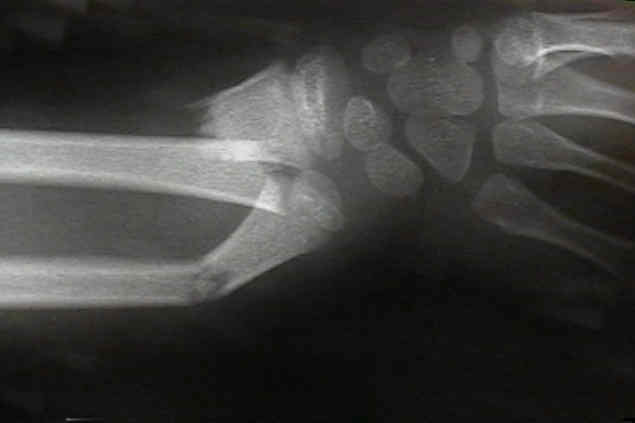

Displaced Distal Third Frx

- angulation up to 20-25 deg during first ten years is OK;

- angulation > 10 deg is unlikely to correct after 10 yrs